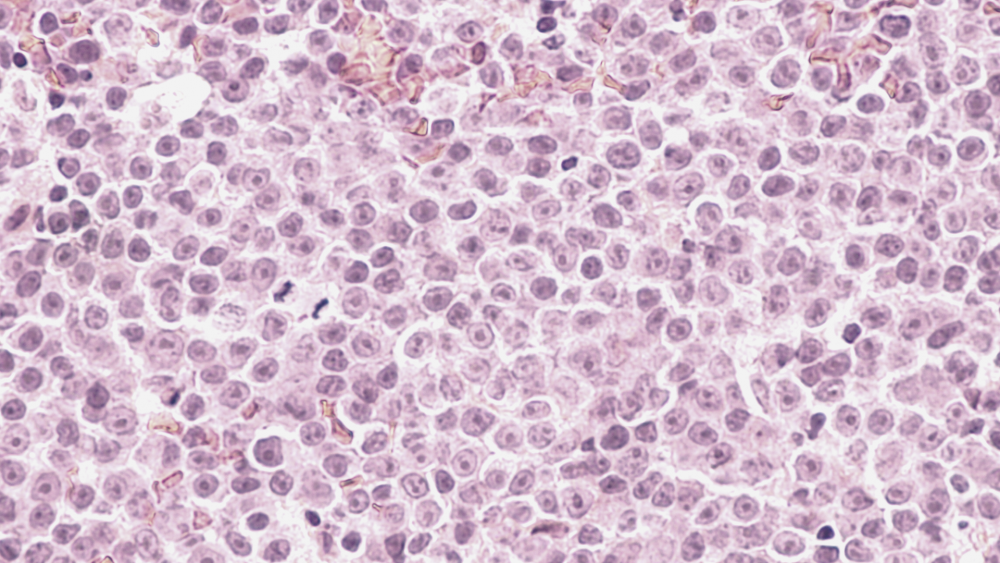

Острые лейкозы

Острые лейкозы развиваются стремительно, в крови человека за короткий срок концентрируется большое количество атипичных клеток.

Хронические лейкозы

Это клональное опухолевое новообразование, которое обусловлено злокачественным перерождением ранних гемопоэтических (кроветворных) клеток и характеризуется постепенным распространением и разрастанием атипичных клеток.

Лимфома Ходжкина

Лимфома — это злокачественное заболевание лимфатической системы, при котором происходит увеличение лимфатических узлов и появление очагов во внутренних органах, зачастую не относящихся к лимфатической системе, из-за того что в них накапливаются опухолевые лимфоциты.

Неходжкинские лимфомы

Неходжкинские лимфомы (НХЛ), в противоположность лимфоме Ходжкина, часто расположены вне лимфатических узлов и склонны к метастазированию, редко ограничиваются одной областью, поражая часто костный мозг и печень.